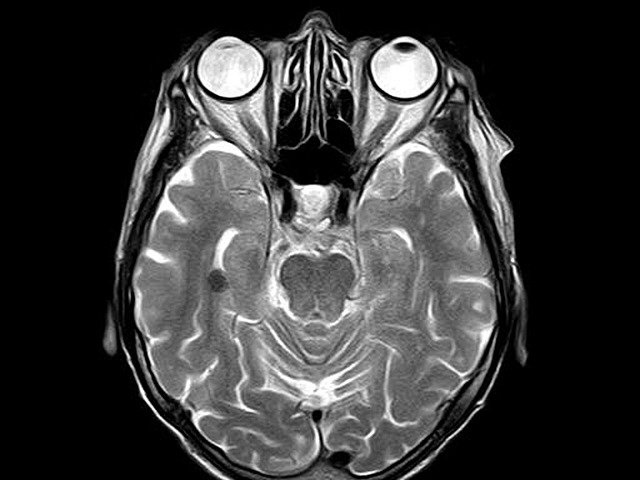

저도 또한 한 때 심각한 어지럼증인지 이석증 때문인지 몸을 못 가눌 정도로 아파서 조금 큰 종합병원에 가서 MRI 뇌검사 + MRA를 받은 적이 있었습니다.

MRI MRA는 아주 살짝 다른데 MRA(Magnetic Resonance Angiography)로 자기공명혈관영상으로 해석되어서 MRI에서 촬영하지 못하는 혈관까지 집중해서 촬영하는 장비입니다.